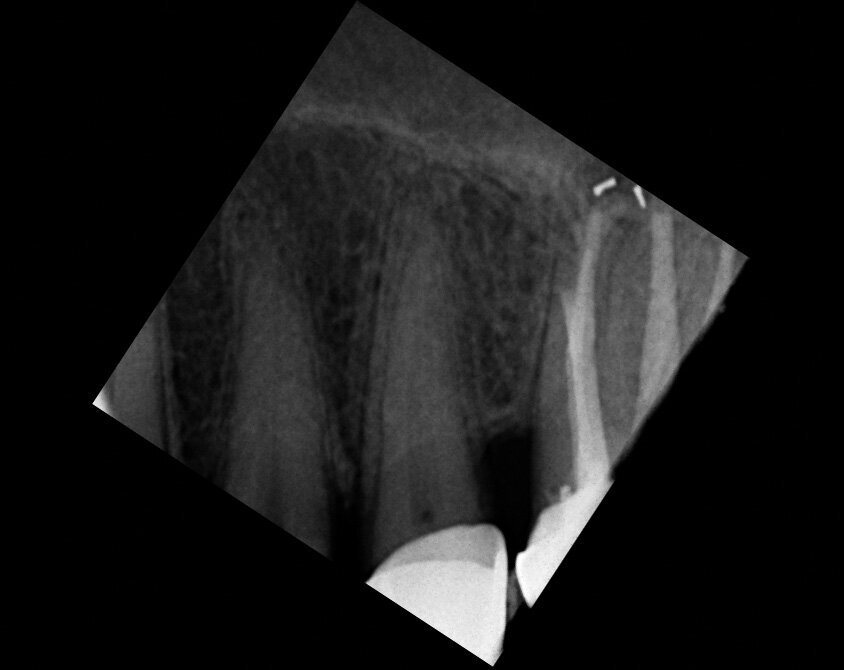

Un patient avait été adressé au cabinet en raison de problèmes associés à la fracture d’une lime. Il était pilote de ligne et se plaignait d’écoulements nasaux purulents lorsqu’il était en vol. La radiographie pré-opératoire (Fig. 1) a distinctement montré la présence de deux fragments d’une lime fracturée dans les canaux mésiaux et d’un cône traversant l’apex de la racine palatine. Après l’imagerie CBCT avec iCAT, il est apparu clairement que le sinus gauche était presque totalement rempli de liquide inflammatoire (Fig. 2) et que le cône présent dans le canal palatin pénétrait dans le sinus. Sur l’image de reconstruction multi planaire (MPR), nous pouvions également distinguer les deux fragments de lime fracturée dans les deux canaux mésiaux (Figs. 3 et 4) et aussi un autre fragment dans le sinus sans aucun contact avec le canal (Fig. 5). L’utilisation de différents filtres nous a permis de visualiser les fragments de lime (Figs. 6–9), ainsi que l’inflammation et le fragment de lime fracturée à l’intérieur du sinus. Nous avons également mieux perçu la position du cône qui émergeait du canal palatin et pénétrait dans le sinus.